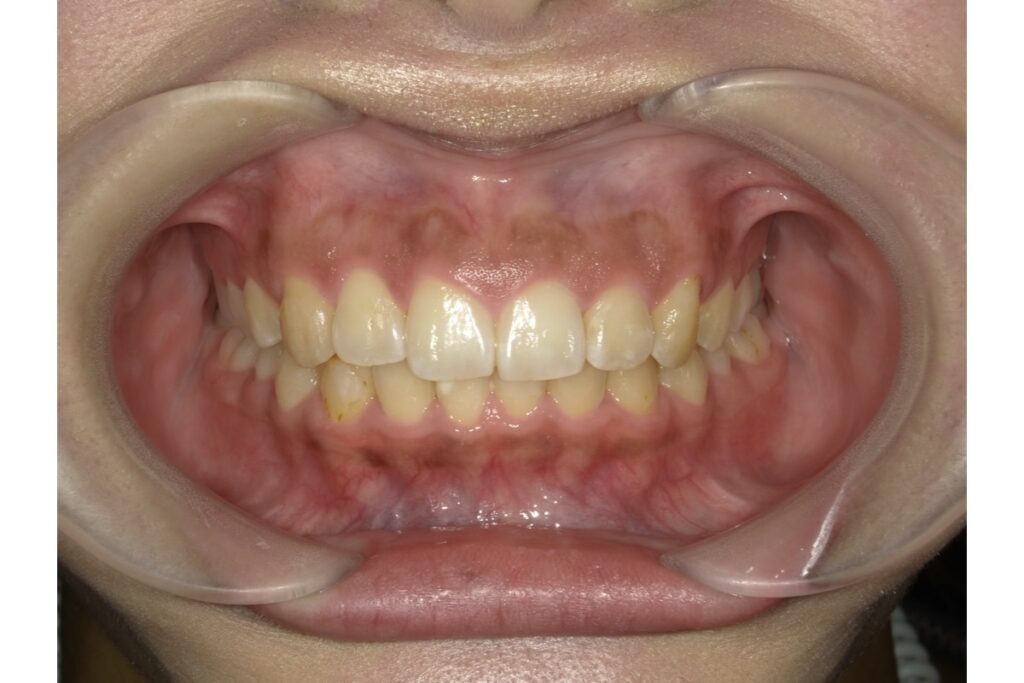

2. 出っ歯(上顎前突)

前歯が前方に突出している出っ歯も、抜歯矯正の対象となることがあります。特に、前歯が唇を押し出している、口が閉じにくい、横顔で口元が突出して見えるなど、見た目や機能的に問題がある場合は、抜歯で前歯を後退させることが有効です。

抜歯矯正は、単に歯を並べるための手段ではなく、全体のバランスや将来の安定性まで考慮した矯正治療の一つの選択肢です。特に、叢生や出っ歯、開咬、口元の突出感などがある場合には、抜歯矯正が効果的なことも多くあります。